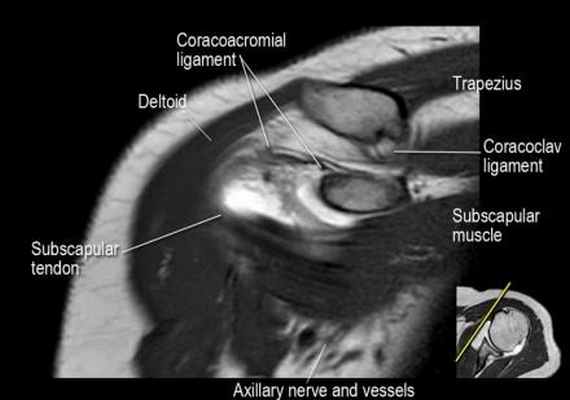

Нормальная корональная анатомия плечевого сустава и контрольный список

- обратите внимание на клювоакромиальную связку (coracoacromial ligament).

- поищите импинджмент надостной мышцы за счет остеофитов в акромиально ключичном суставе или из-за утолщения клювовидноакромиальной связки.

- поищите скопление жидкости в подакромиальной сумке и повреждение сухожидия надостной мышцы

- поищите частичный разрыв сухожилия надостной мышцы в месте его прикрепления в виде кольцевидного повышения сигнала

- поищите повреждение сухожилия подостной мышцы